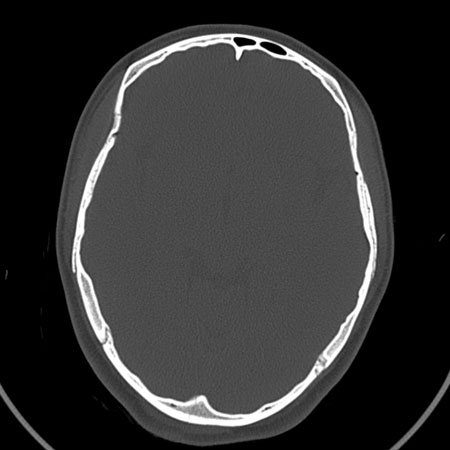

请问各位战友:图示箭头处是否为颅骨骨折?

病史:患者,女,20岁.头部及腹部外伤20分钟.伤后昏迷,无呕吐.头及右侧腰背部疼痛,双侧瞳孔等大,

右肾区叩痛.其它无异常.患者家属否认原有外伤史.

请大家看看是否为颅骨骨折.还是正常变异,或为陈旧骨折.谢谢.

图片未上传完,所见图象示枕骨线样低密度影,边缘锐利,结合外伤史,伤后昏迷,骨折不能除外。

枕骨的线样低密度影锐利、清晰,但正好位于矢状缝的位置,局部无明显软组织肿块,相临及对冲部位脑实质亦无出血及挫裂伤表现。

单就这几层暂不考虑骨折,建议上传完整图片。

楼主所关心的另一个线样影应该是头颅矢状面略偏左,射线正好穿过所致,不需要考虑骨折。

枕骨是单块的,矢状缝是在顶骨而不是在枕骨,枕骨后缘见线状低密度,边缘税利,考虑在骨折存在。

枕后部及左侧颞枕部边缘锐利的线样低密度影,局部软组织无异常,左侧乳突蜂房密度均匀,硬膜下及脑实质内未见出血灶,考虑为正常变异。

枕部考虑骨折。一般的颅逢不会跨越板障,楼主所示枕骨断面两侧板障也不连续。

需注意软组织改变和皮质是否存在,如果皮质存在,线影锐利,既使局部外伤,亦不应诊为骨折,请酌!

另外,本例扫描体位不正,亦为影响判断之重要因素如颞枕缝!